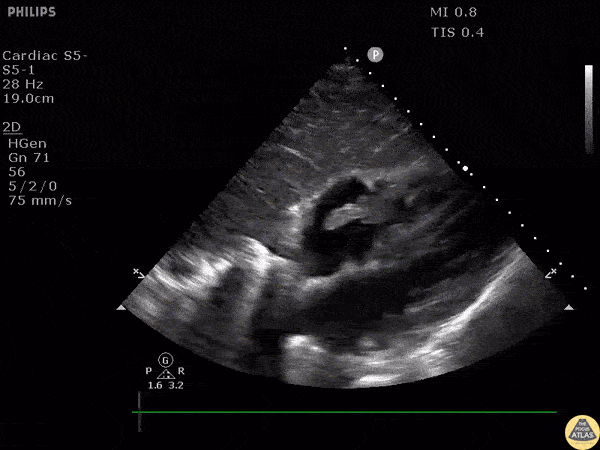

Tricuspid valve endocarditis seen in a patient with IVDU. This subcostal view allows great visualization of the tricuspid valve when using the liver as an acoustic window. Image courtesy of Robert Jones DO, FACEP @RJonesSonoEM Director, Emergency Ultrasound; MetroHealth Medical Center; Professor, Case Western Reserve Medical School, Cleveland, OH View his original post here